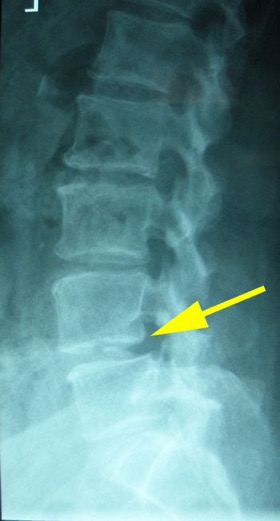

CT was ordered and shown Spinal Canal Stenosis at L4 5, and a left-sided disc prolapse with impingement of the left L4 root.

IMAGING